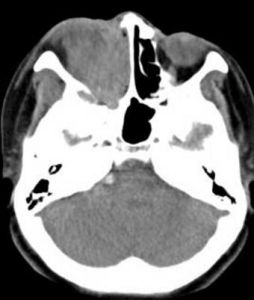

影像症狀

嗅神經母細胞瘤X線特點包括"亞鈴形"腫塊,腫物延伸穿過篩板。病變範圍在MRI的T1加權像和在T1加權像基礎上注射釓標記增強後的T2加權像的前後對比中可非常好的顯示出來。骨侵蝕的細微改變(紙樣板,篩板和篩凹)在CT掃描中能很好顯示,在X線片中可見鈣化引起的斑點狀形態。血管造影可發現病變為血管增生性腫瘤。

嗅神經母細胞瘤的X線特點包括“啞鈴型”腫塊,腫物延伸穿過篩板,病變範圍在MRI的T1加權像和T2加權像的前後對比中科非常好的顯示出來。骨侵蝕的細微改變(紙樣板、篩板和篩凹)在CT掃描中能很好顯示,在X線片中可見鈣化引起的斑點狀形態。血管造影可發現為血管增生性腫瘤。